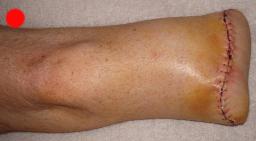

Postoperative (12th) images of left ankle

The images displayed here were created at various appointments following surgery performed by Dr. Daniel Saunders. In the X-Ray you can see

where Dr. Saunders has removed the fibula plate, joined the tibia and fibula with a screw, built-up the area of the tibia where previously

there was considerable absence of bone and lastly added the EBI OsteoGen-M Bone Stimulator (dual lead). The photos show the left side site

where the fibula plate was removed, the top site where donor bone, bone filler material and the stimulator were added and the right side

where the tissue has burst because of swelling. Liam was placed on an IV drip of Vancomycin following surgery to combat the potential onset

of Osteomyelitis. The image of the cast includes the fibula plate that was removed during surgery. The next images were taken later and show

that the staples and stitches were removed. In one of the images, you can see Liam's wife Madeline helping with leg cleanup and in one image

can be seen the EBI representative after being put to work (holding up the left leg while the latest cast cures) by Dr. Saunders. Later shots show

a healing tissue burst site with some overgrowth and Dr. Saunders cauterizing the overgrowth. Bones shifting too much (shown in X-Rays). The

last images are of the left ankle prior to the 13th surgery.